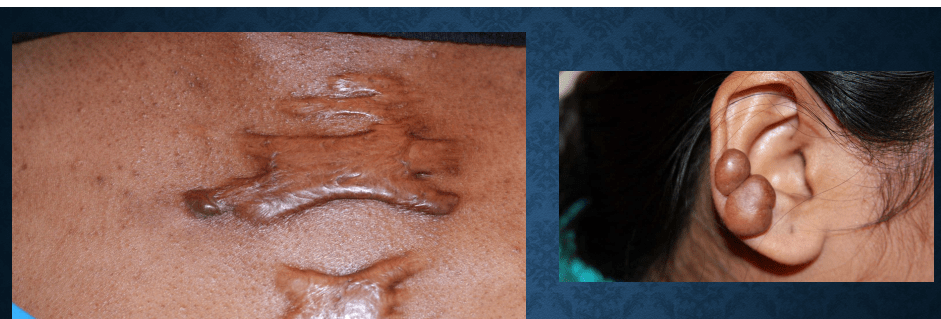

dermatofibroma

keloid